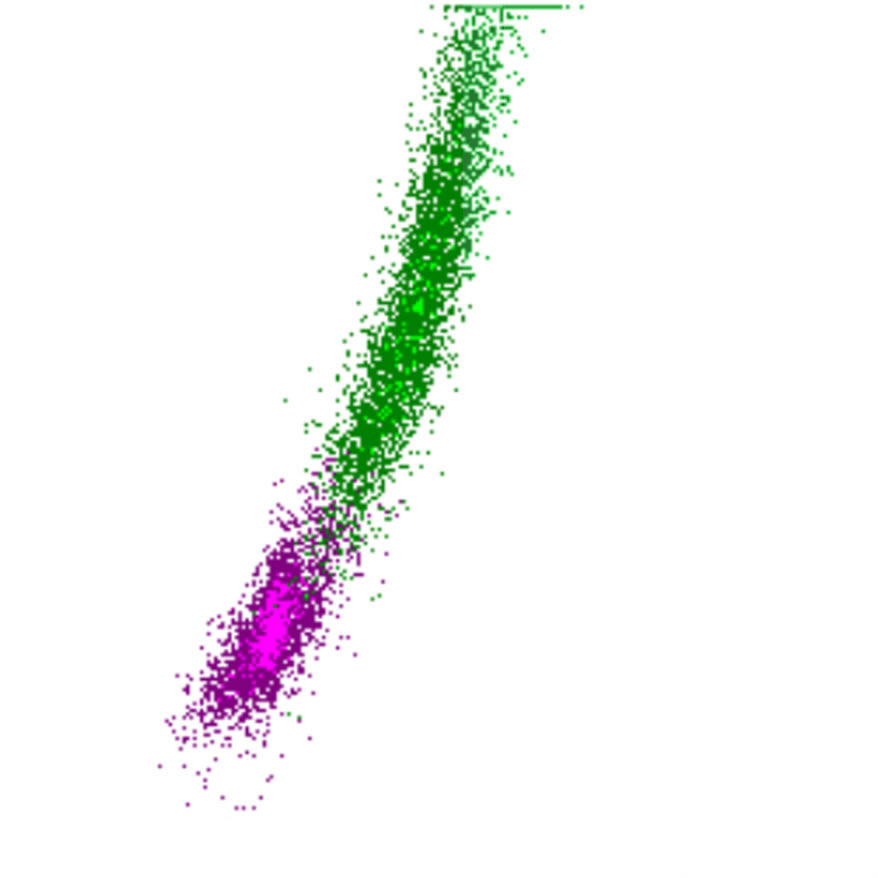

Side Fluorescence

Le signal SFL reflète la teneur en acides nucléiques des cellules. Les cellules avec un SFL élevé contiennent davantage d’ARN et/ou d’ADN, ce qui indique souvent une activité ou une prolifération accrue. Il existe une corrélation limitée entre le SFL et le FSC ; bien que les cellules plus grandes présentent généralement un SFL plus élevé, des exceptions existent, telles que des blastes avec un SFL relativement faible ou des lymphocytes activés avec un SFL élevé malgré leur plus petite taille.

SFL scatter

SFL faible

SFL élevé